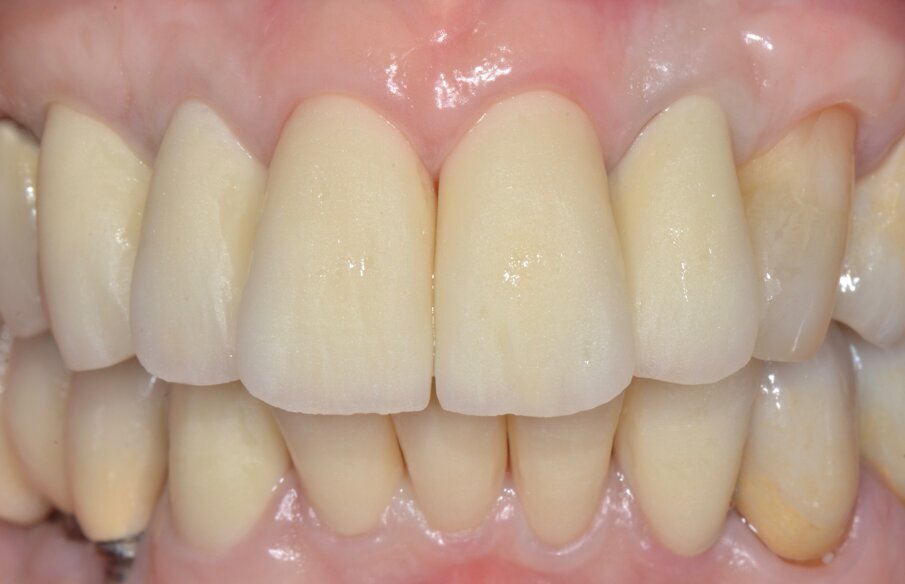

Inizialmente vengono applicati i provvisori prelimatura (Fig. 9) utilizzati anche come mock-up per passare dopo le opportune valutazioni estetiche (Figg. 10, 11) a una seconda serie di provvisori che ci accompagnaranno durante la fase chirurgica e il tempo di guarigione e maturazione dei tessuti. Prima si procede con la chirurgia resettiva (ORS) sul canino superiore destro per alzare la parabola gengivale a livello degli altri denti frontali; questo intervento viene eseguito con un approccio “delicato” e meno invasivo possibile per non penalizzare l’estetica della corona preesistente sul primo premolare superiore destro.

Dopo circa un mese viene eseguito un lembo a scorrimento coronale con innesto di tessuto connettivo (CAF+CTG) prelevato dal palato con la “Tecnica di Langer e Langer mod. J.Bruno” per coprire la recessione sul canino superiore sinistro e ispessire il tessuto sopra il quale verrà posizionata una faccetta in ceramica (Figg. 12-17). A due mesi dal CAF+CTG si può notare la maturazione dell’innesto con un ottimale spessore mantenuto e lo spazio guadagnato sul canino controlaterale con la ORS (Figg. 18, 19).

Valutiamo di aver raggiunto una buona simmetria delle parabole gengivali per cui si può procedere con la finalizzazione protesica (Fig. 20). I monconi sono stati preparati con una preparazione verticale per dare priorità alla robustezza dei monconi stessi nella zona cervicale (Figg. 21, 22).